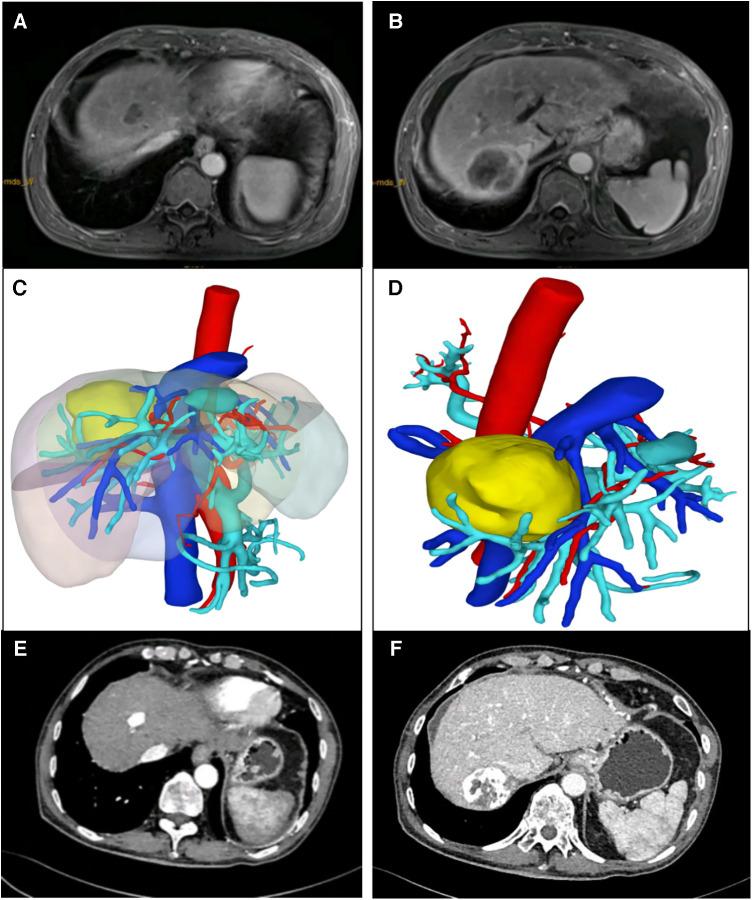

Forty-five consecutive patients with multiple HCCs who met the inclusion criteria received downstaging treatment with TKIs plus anti-PD-1 antibodies combined with TACE. Nine patients were successfully downstaged and met the R0 resection criteria, and 8 patients underwent surgery. Among the patients, 5 patients had BCLC stage C, and 3 patients had BCLC stage B. There were 2 lesions in 5 patients, 3 lesions in 2 patients, and 4 lesions in 1 patient. The average size of the main HCC was 8.5 cm (range: 5.4-9.1 cm), and the diameter of the remaining HCCs was 1.6 cm (range: 0.8-2.9 cm). The average time from the start of downstaging therapy to surgery was 81 days (range: 60-210 days). All 8 patients underwent LH of the main HCC, and the remaining HCCs were targeted with RFA. The mean operation time was 220 min (range 150-370 min), the average intraoperative blood loss was 260 ml (range 100-750 ml), there was no case conversion to laparotomy, and the average postoperative hospital stay was 9 days (range 7-25 days). The incidence of postoperative complications was 37.5% and there were no deaths. The average follow-up time was 18.2 months (range 6.1-22.4 months), 5 patients survived tumour-free, 2 patients had tumour recurrence, and 1 patient died.

45例符合纳入标准的连续多发性肝癌患者接受了TKIs联合抗PD-1抗体并结合TACE的降期治疗。9例患者成功降期并符合R0切除标准,8例患者接受了手术。患者中,5例为巴塞罗那临床肝癌(BCLC)分期C期,3例为BCLC分期B期。5例患者有2个病灶,2例患者有3个病灶,1例患者有4个病灶。主要肝癌的平均大小为8.5 cm(范围:5.4 - 9.1 cm),其余肝癌的直径为1.6 cm(范围:0.8 - 2.9 cm)。从降期治疗开始到手术的平均时间为81天(范围:60 - 210天)。所有8例患者均接受了主要肝癌的LH,其余肝癌采用RFA靶向治疗。平均手术时间为220 min(范围150 - 370 min),平均术中出血量为260 ml(范围100 - 750 ml),无病例转为开腹手术,平均术后住院时间为9天(范围7 - 25天)。术后并发症发生率为37.5%,无死亡病例。平均随访时间为18.2个月(范围6.1 - 22.4个月),5例患者无瘤生存,2例患者肿瘤复发,1例患者死亡。